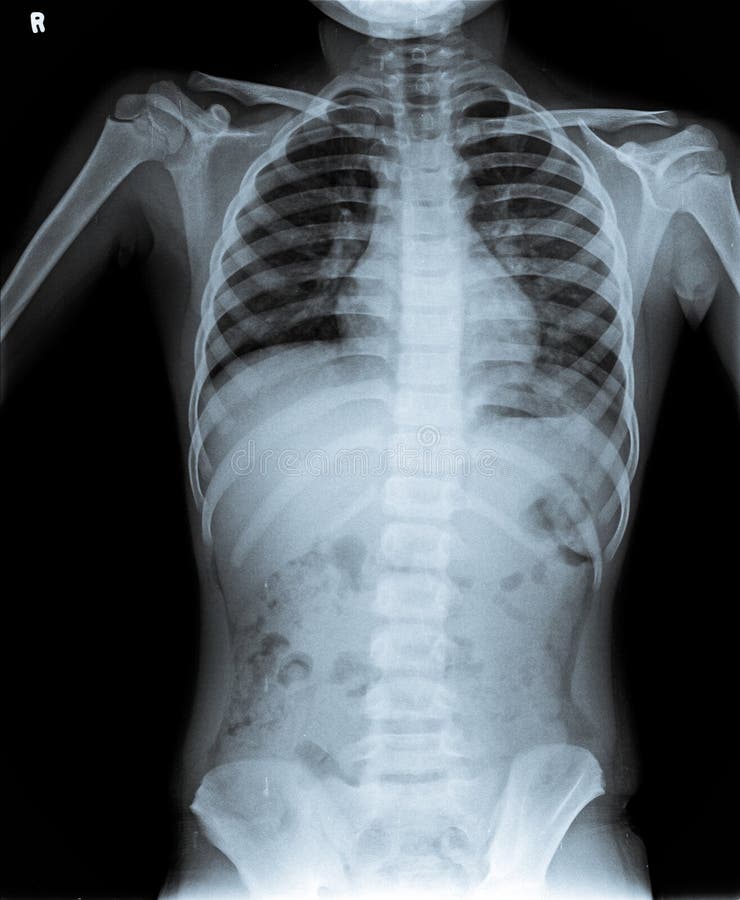

Infant Chest X Ray Normal . The degree of rotation is best assessed by comparing the length of the anterior ribs visible on both sides. Chest radiograph reveals diffuse coarse irregular opacities and. Radiopaedia provides detailed information on interpreting neonatal chest radiographs in exam settings, including common techniques and. Performing chest radiography on pediatric patients can be for a number of indications 1: This article lists examples of normal imaging of the pediatric patients divided by region, modality, and age. After these steps, the chest film can be interpreted for pathology. This is done in a stepwise manner:

Normal Chest X Ray of Human Child. Stock Image Image of lungs Infant Chest X Ray Normal After these steps, the chest film can be interpreted for pathology. The degree of rotation is best assessed by comparing the length of the anterior ribs visible on both sides. Radiopaedia provides detailed information on interpreting neonatal chest radiographs in exam settings, including common techniques and. This article lists examples of normal imaging of the pediatric patients divided by region,. Infant Chest X Ray Normal.